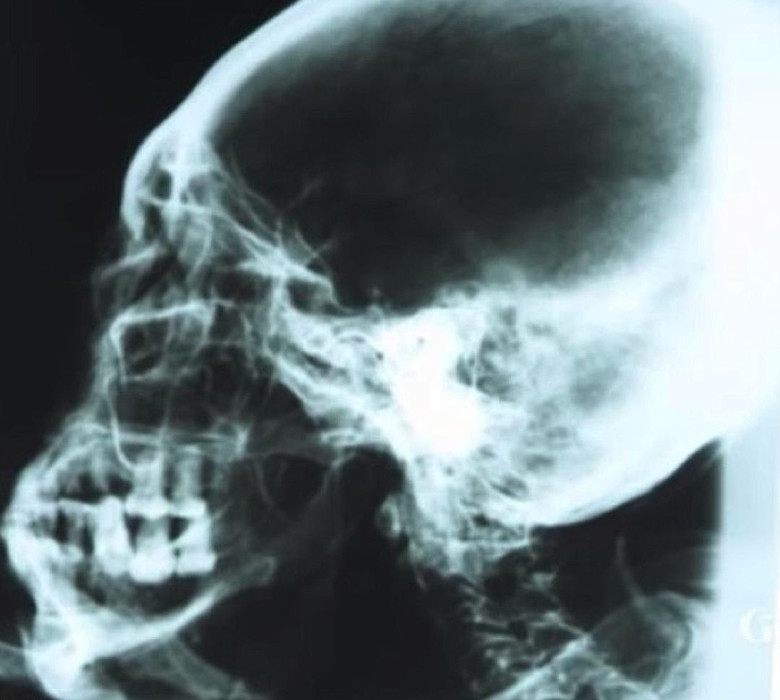

Kako je rekla N. Zaloznaya, proporcije tijela ove mumije su, uglavnom, čisto ljudskog rasta, rast humanoida iznosi 168 centimetara. Ali ovdje glava i udovi, naravno, iznenađuju. Lobanja je izdužena, izdužena leđa, nos je sićušan, praktično nema ušiju umesto njih – male rupe u lubanju.

Mumija je posuta nekim prahom (utvrdio je profesor Korotkov da je balzamirajuća tvar), pa se na prvi pogled čini gipska skulptura, doduše rendgenska, poput računara tomografija, pokazana – unutra je normalan kostur, a takođe ostaci unutrašnjih organa. Prema radiokarbonskoj analizi određuje se starost mumije – 2300-2500 godina.